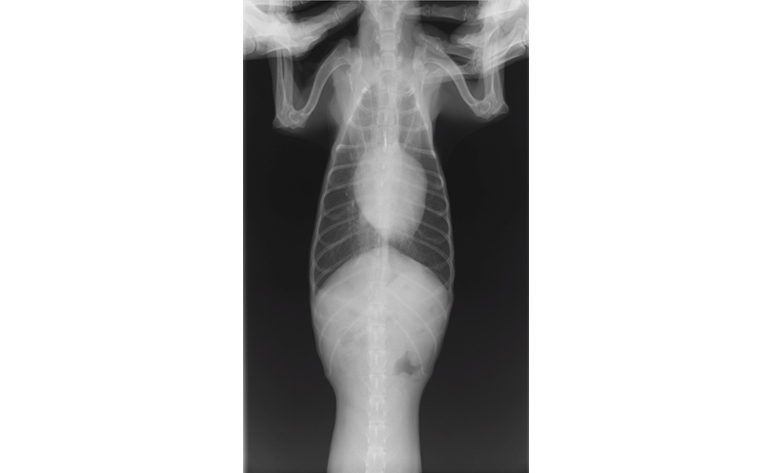

| 検査 | 身体検査、聴診、レントゲン検査、超音波検査、心電図検査、血圧測定、血液検査 |

症状や検査結果を基に、薬の種類や量を決めていきます。また、病状の進行によって種類、量が変わるので、定期的な検査をします。

心臓病の検査で特に大きな要となるのが、超音波検査でありますが、大変高い技術が求められる検査であります。この技術により診断が左右することも大いにあります。当院では幅広い知識と高い技術で検査を行い、診断しております。この検査では、動物に横になったり、仰向けになったりしてもらいますが、その姿勢が苦手な子、またその姿勢によって息苦しくなってしまう子に対しては、立ったままの姿勢での検査を行っております。